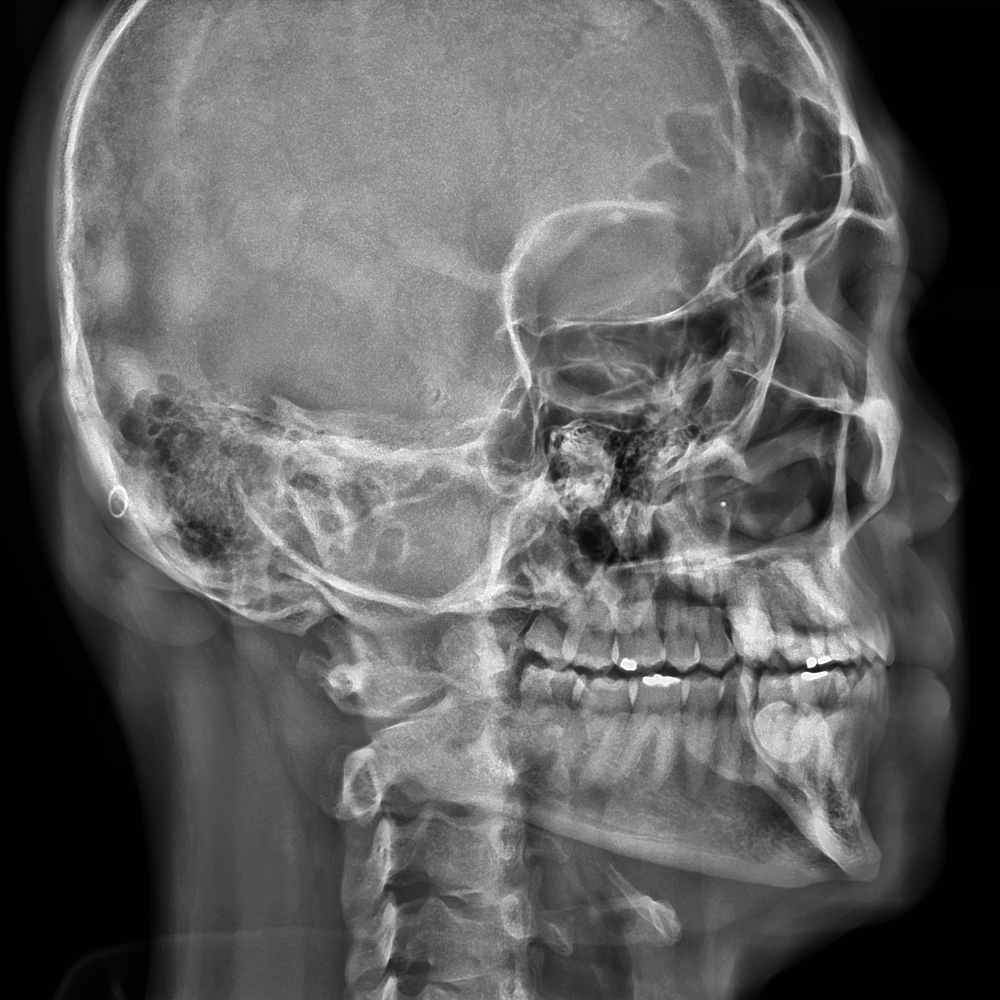

El Eagle 2D Pan/Ceph ofrece todos los exámenes en el perfil panorámico

(panorámica estándar, senos maxilares, baja dosis, bitewing, ATM, ortogonalidad perfeccionada, panorámica infantil y bitewing ortogonalidad perfeccionada)

y todos los exámenes en el perfil cefalométrico (Posteroanterior, Antero-posterior, 45 Grados, Lateral, Carpal, PA de Walters, Axial Bazal, Hirtz).